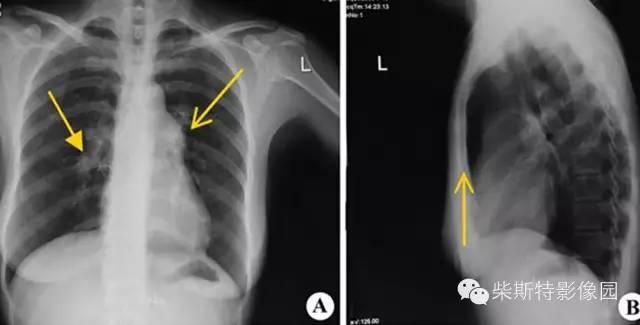

胸部X线片

两肺纹理稀疏,肺动脉段突出